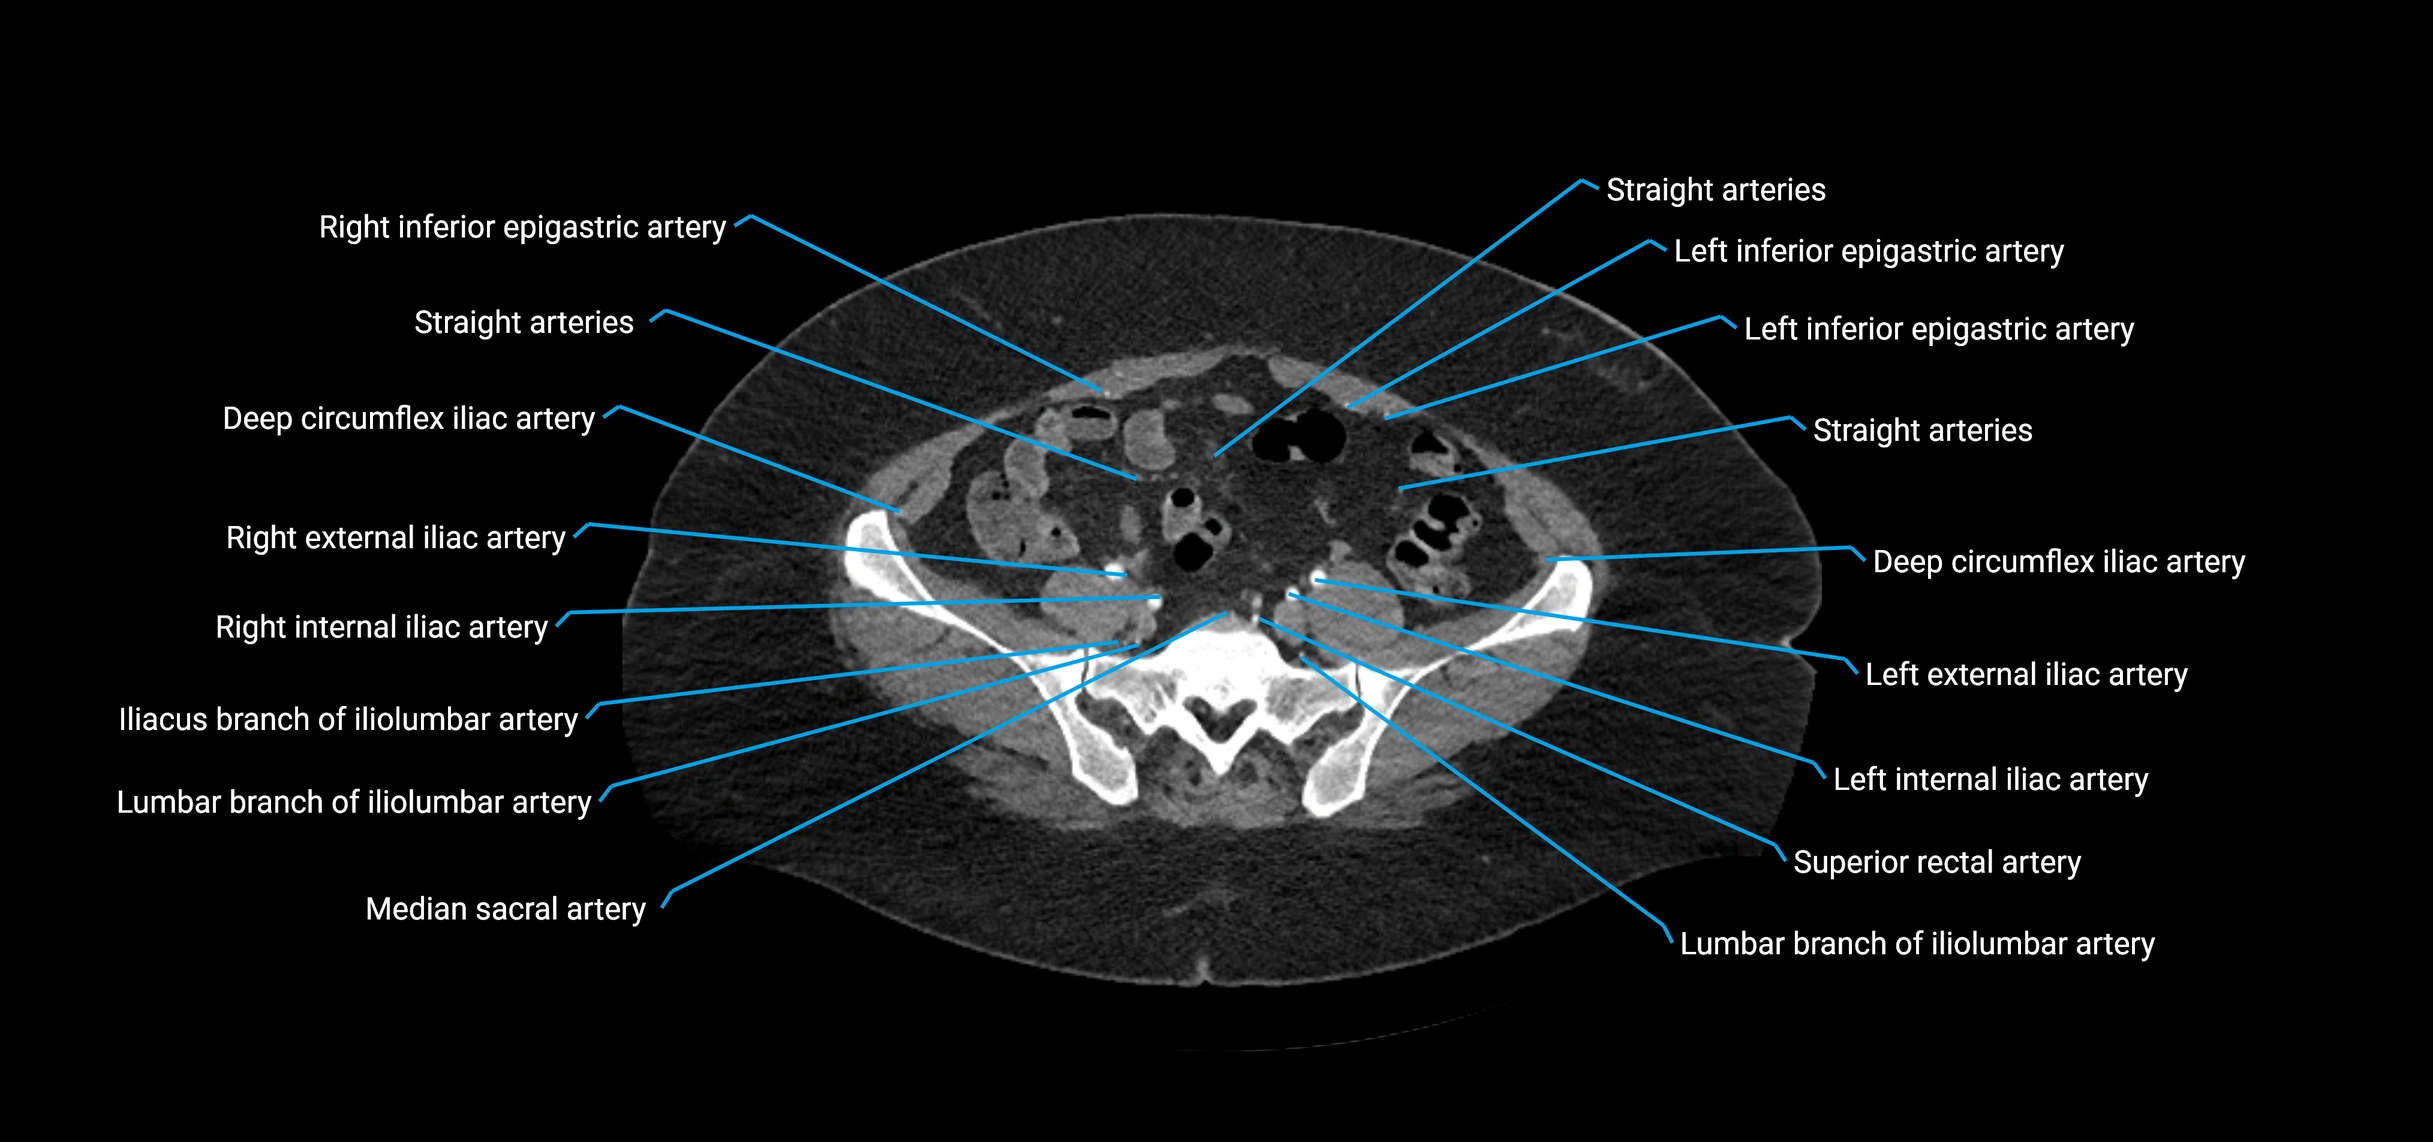

CT images

image

Contrast-enhanced CT (CTA):

• Gold standard for abdominal aortic imaging

• Provides excellent detail of lumen, wall, aneurysm, thrombus, and branch vessels

• Multiplanar and 3D reconstructions help in aneurysm measurement, stent graft planning, and dissection evaluation